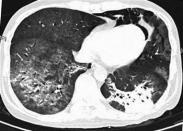

肺部感染治療

• 肺部感染

628健康網為您分享有關肺部感染的癥狀,肺部感染的治療方法,肺部感染的預防知識,肺部感染的癥狀圖片,肺部感染吃什么藥,肺...